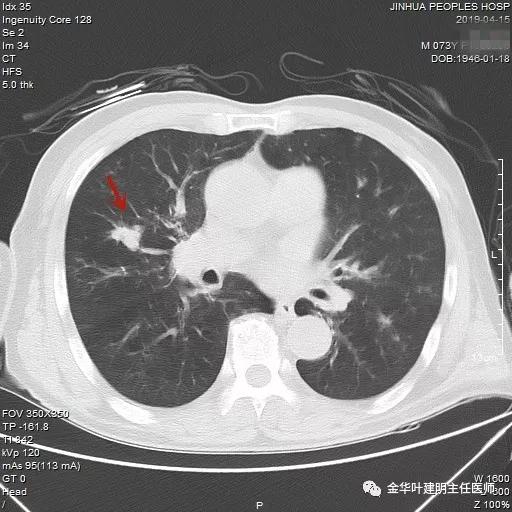

武义的吴某,今年已经73岁了,患有慢性支气管炎与肺气肿多年,每到天气转凉就要胸闷、气急及咳嗽、咳痰发作,严重时还有喘憋症状,每年都要住院1-2次。今年4月份的时候吴某又因慢支急性发作来我院呼吸内科住院。常规检查时发现右肺上叶有一实性结节,约1.5厘米大小,有毛刺及浅分叶,考虑肺癌可能性大,医生建议其行肺穿刺活检。当时图片如下: